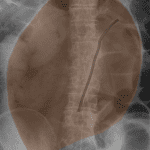

- Marked gaseous distension of the colon with a twisted appearance of the sigmoid colon and relatively gasless rectum

- Sigmoid volvulus

Marked gaseous distension of the colon with a twisted appearance of the sigmoid colon and relatively gasless rectum, concerning for sigmoid volvulus. Recommend surgical consultation and consideration of CT for further evaluation.